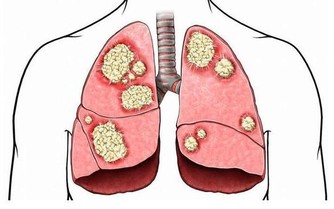

尿酸結晶沉積於腎臟,可導致急、慢性尿酸性腎病和尿石症。大量尿酸結晶沉積在腎小管等處,造成急性尿路梗阻,會突然出現少尿、無尿、急性腎功能衰竭等症狀,所以,一旦出現這類情況,也要警惕尿酸高了。

患高尿酸血症10~2O年的患者,由於結晶長期沉積於腎間質,導致慢性間質性腎炎,可出現夜尿增多、尿比重下降、輕到中度蛋白尿,也就是慢性尿酸性腎病的表現。